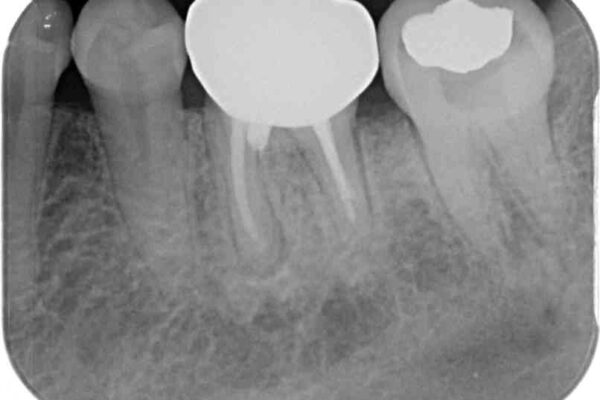

以前むし歯治療をした後から定期的に痛むことがあるとのことで、レントゲン写真より神経組織が失活していることが予想されました。

銀歯を外すと神経組織の一部が取り除かれており、歯根に付け根に穴が空けられている状態でした。

出血の原因は以前の治療で空けられた穴であると考え、封鎖をするとともに根管治療を行い、その後オールセラミッククラウンにて補綴治療を行うこととしました。

術後6ヶ月でレントゲン写真を撮影したところ、出血の原因であった穴付近の溶けていた骨が回復している様子が認められました。